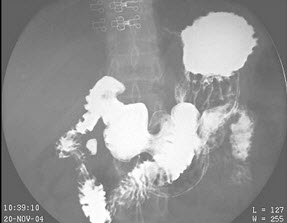

28、单项选择题

女,48岁,常感中上腹不适,无返酸、嗳气及黑便史,结合图像,最可能的诊断为()

A.正常肠圈

B.十二指肠炎

C.球部溃疡

D.降段憩室

E.水平段憩室